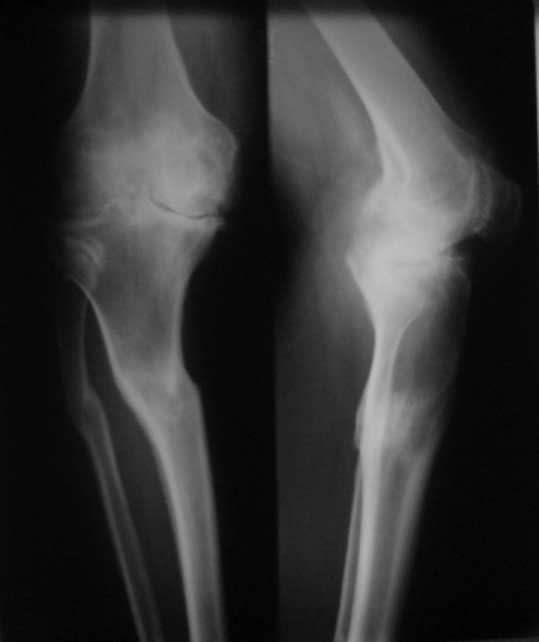

У пациента 50 лет имеется разгибательная контрактура через 8 меспосле ТКА. Уважаемые коллеги. Пациент 8 мес после операции ТКА, в анамнезе – неправильно сросшийся перелом голени, коррекция оси (снимки прилагаются. В настоящее время имеется разгибательная контрактура 10/5/0, на операционном столе было 90/0/5, на момент выписки движения 50/0/0 в надежде на дальнейшую разработку. До эндопротезирования 40/10/0. Глубокая инфекция исключена. Ротация бедренного компонента в норме (по КТ). Вопросы: насколько для такого ограничения критична некорректная установка б/б компонента (я намерял 7 град)? Причина нынешнего состояния, артрофиброз? Какие действия следует предпринять, удаление рубцов, релиз головок 4-главой мышцы? Что-либо другое, ваше мнение? С уважением, Максим Агалаков, Екатеринбург.

а вы уверены, что это артрофиброз, а не patella baja

Рентгеновский снимок хороший, операция выполнена достойно, надколенник не смущает. Остаюсь на своем мнении, артролиз, если смущает давление надколенника при артроскопии помимо артролиза верхнего заворота, боковых каналов и переднего отдела, дополните латеральным релизом надколенника, чтоб уменьшить натяжение.

Низковат, соласен. Соориентируетесь при операции, если ограничивает движения, перенести бугристость или Z-образная тенотомия связки надколенника, артросокпический артролиз обязательно.